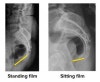

실제 꼬리뼈의 골절은 흔하지 않고, 수술적 치료를 요하지는 않습니다. 골절이 없더라도 통증이 매우 클 수 있고, 골절이 있더라도 증상이 심하지 않다면 큰 상관 없습니다. 어떤 경우는 앉아 있는 것이, 어떤 경우는 앉거나 일어서는 통증을 유발합니다.

최근에는 보험 등의 이유로 골절인지 아닌지 분명하게 밝히는 것이 중요할 수도 있지만, 치료방침은 미골의 골절 유무에 달라지지 않는데, 실제 꽤 많은 움직임이 있기도 하고, 달리 고정하거나 수술할 수 있는 도구도 없기 때문입니다. 여러 가지 이유로 골절인지 아닌지를 분명히 밝혀야 한다면, CT 등이 필요할 수도 있습니다.